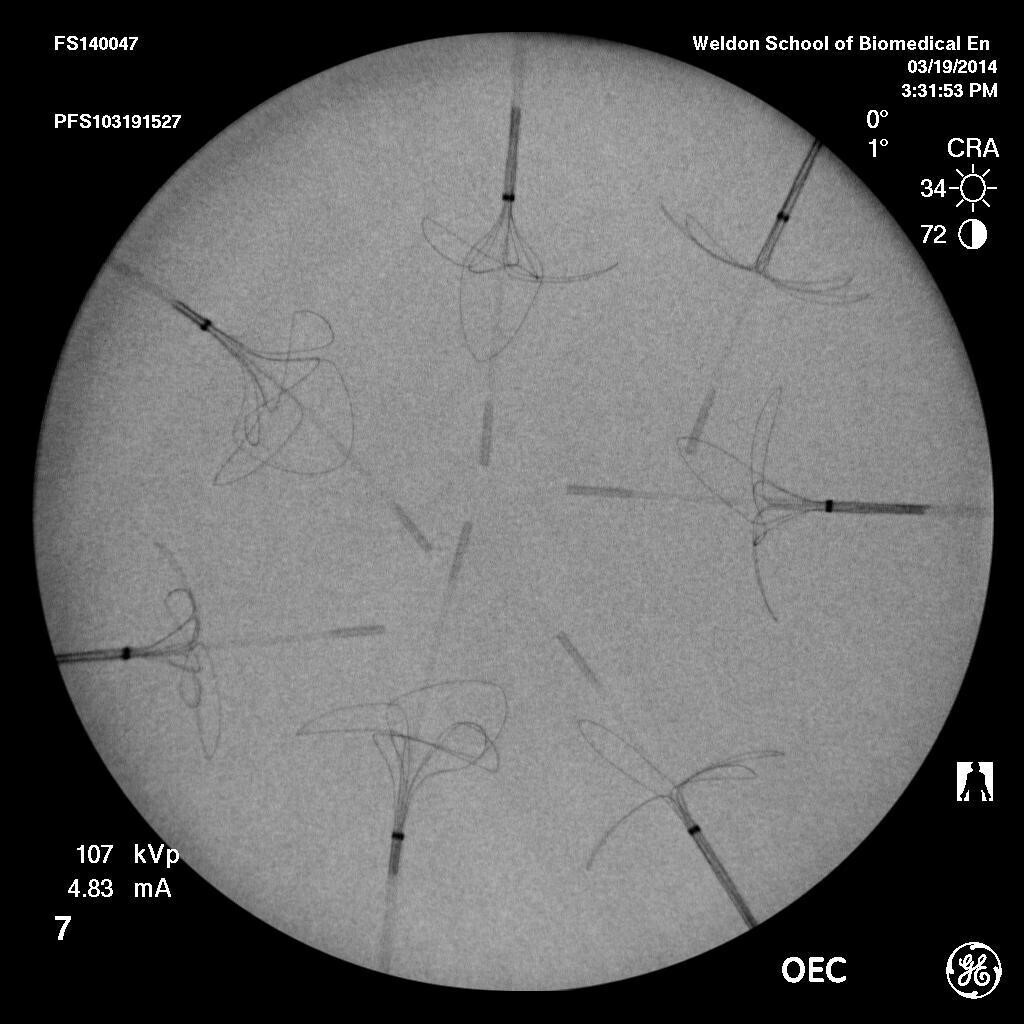

Radiopacity is the ability of a material to impede the passage of x-rays, thus allowing for visibility in an xray. This allows for devices to be tracked in vivo during a medical procedure. Radiopacity of a test article can be determined either qualitatively or quantitatively. Qualitative radiopacity compares visibility of a test article to a reference, such as a predicate device. Quantitative radiopacity calculates the difference in pixel intensity between the test article and the reference. Pixel intensity is defined as the greyscale value of a pixel between 0 and 255, with 0 representing black and 255 representing white. The lower the pixel intensity, the higher the radiopacity, and the more visible your device. Evaluating the radiopacity of medical devices is important to the development process since it verifies that the device will be adequately visible during a procedure. Figure 1 shows an example of medical devices arranged on a phantom, which mimics a portion of the body during radiopacity evaluation.